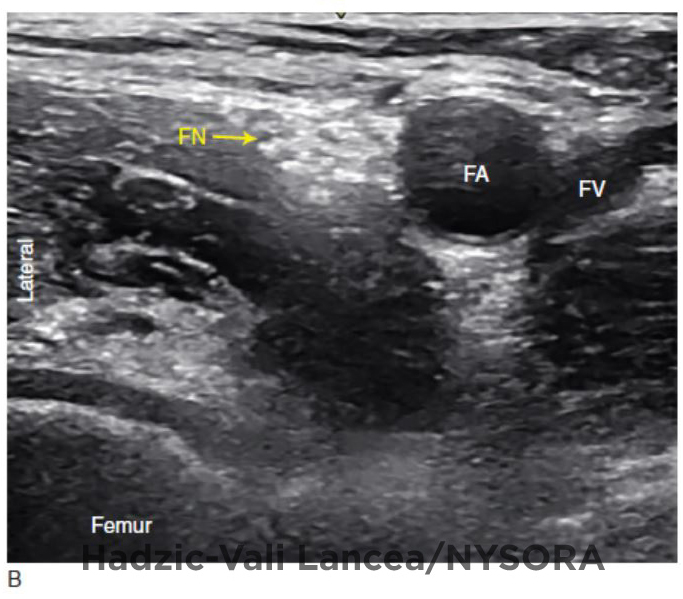

Figure 2 from Femoral Nerve Blocks Semantic Scholar Lower Extremity Nerve Blocks Ppt It begins with an introduction on spinal and epidural anesthesia commonly used for lower. 13 likes • 1,749 views. It describes the lumbar and sacral plexuses,. This document provides information on peripheral nerve blocks for the lower extremities. Us guided lower limb nerve blocks | ppt. General considerations for lower extremity blocks • le blocks. The lumbar plexus consists of. Lower Extremity Nerve Blocks Ppt.